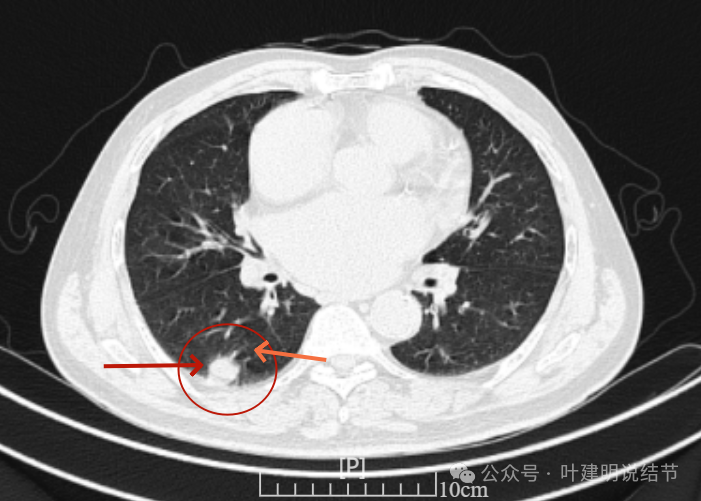

增强纵隔窗见病灶内部的密度好像低于周围区域,像坏死。

邻近胸膜无牵拉,灶内有低密度区,局部有点状液性密度。邻近胸膜较为广泛的增厚或胸膜反应。

病灶与胸膜接触面宽,病灶内部密度较低。